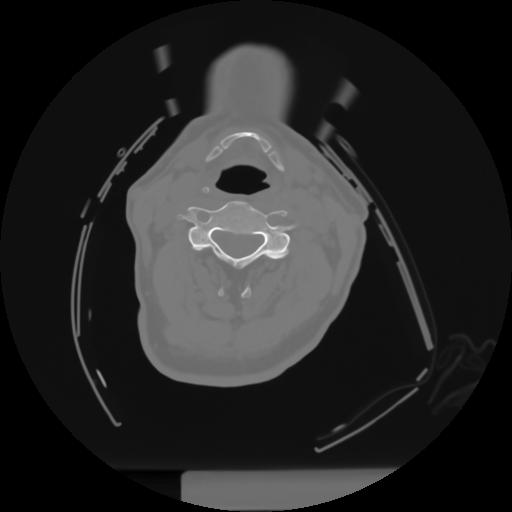

10 P.BLANDAS,,Axial,2.0,P.BLANDAS,,